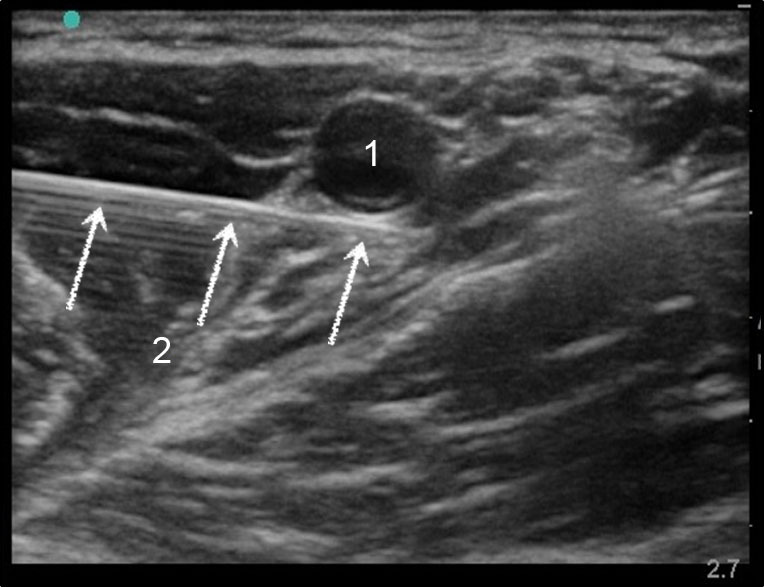

Axillary Needle Injection Image

Artery

Needle